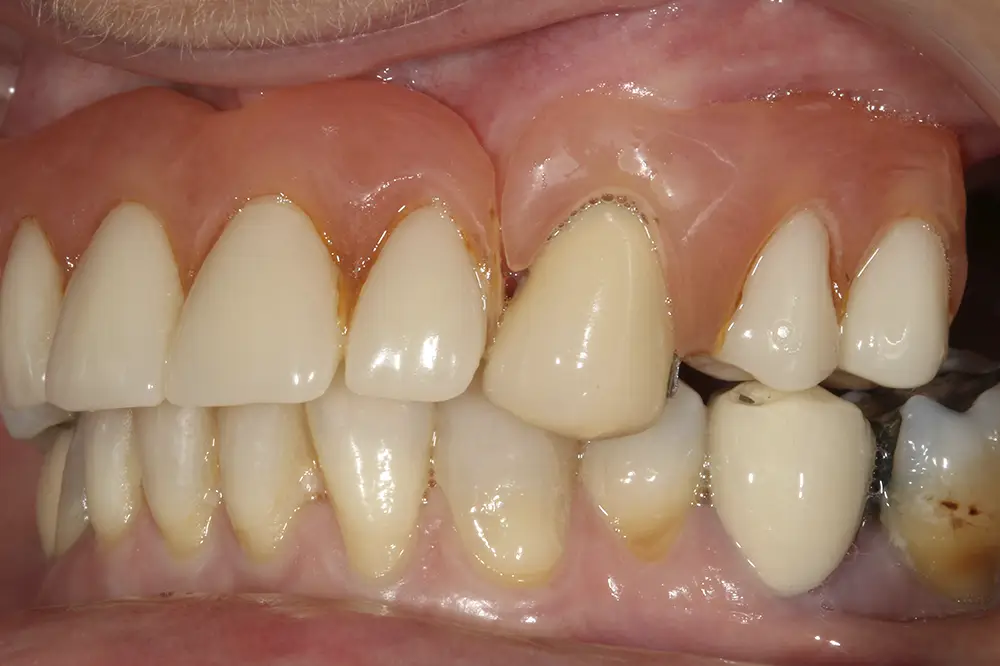

Al retirar las prótesis en las imágenes laterales, observamos además un colapso de la zona anterior y recesiones en todas las piezas que aún conserva la paciente (figs. 5 y 6). En la radiografía inicial observamos pérdidas óseas elevadas en el molar del primer cuadrante y el premolar de este mismo sector, por lo que se decide su exodoncia y regeneración con PRGF, que se realizará el mismo día de la primera fase de inserción de los implantes. En el arco inferior hay también problemas con los sectores posteriores, con pérdidas óseas en el cuarto cuadrante y signos de fractura vertical en el puente 44-46 y caries radicular en las piezas 35 y 36 (fig. 7). Por ello, estas piezas inferiores son también candidatas a la exodoncia, regeneración y reposición con implantes dentales, para lograr una posterior rehabilitación funcional.

Figs. 5 y 6. Imágenes laterales de la paciente sin su prótesis. Al retirarla, se hace evidente el colapso de la dimensión vertical y la pérdida ósea y recesión de los dientes pilares que sostienen la prótesis removible.